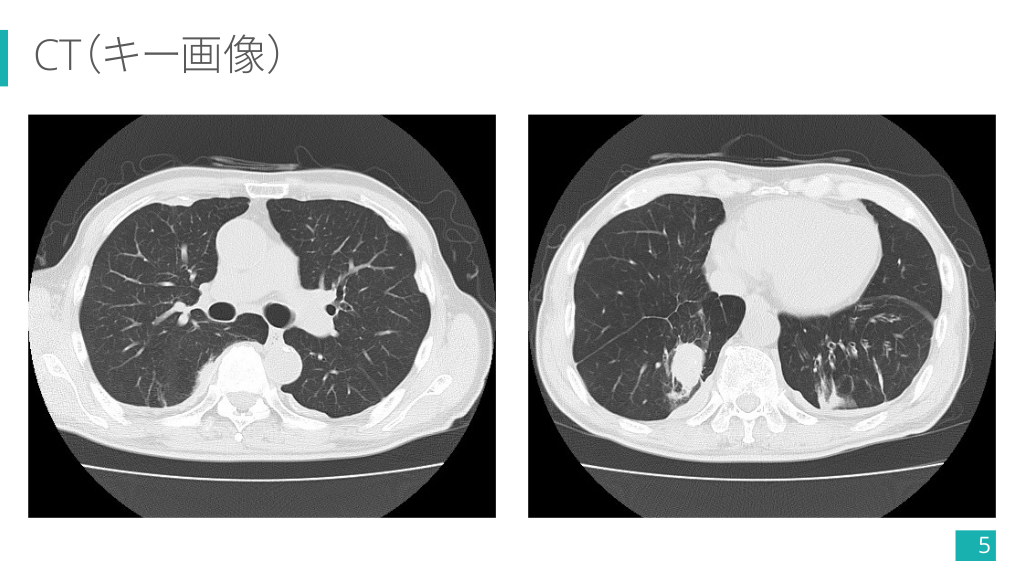

CT(キー画像) 5

CT(キー画像) 多発胸膜プラーク(一部石灰化+) 右肺下葉の卵円形腫瘤 14

CT(キー画像) 腫瘤へと曲線的に収束する気管支血管束 (comet tail sign) 15

1-5) 円形無気肺の画像診断 Ø 肺野末梢に位置する円形/卵円形 の結節影・腫瘤影. Ø 肺の容積減少や胸水,胸膜プラー クなどの随伴所見を確認する. Ø 胸膜プラークは横隔膜面に着目!! 4) より引用 Case courtesy of Dr Matthew Lukies, Radiopaedia.org, rID: 45643 26

1-5) 円形無気肺の画像診断 Ø 両肺下葉に多い. Ø 単発 > 多発・両側性. Ø 2.5 cm 〜 5.0 cm 程度の大きさ のものが多い. Ø 経時的に増大せず縮小することも. Ø 胸膜プラークや石綿肺など アスベスト関連疾患の有無も重要. 4) より引用 Case courtesy of Dr Hidayatullah Hamidi, Radiopaedia.org, rID: 90658 27

1-5) 円形無気肺の画像診断 Ø 肥厚した胸膜から連続し,胸膜と 鋭角をなす円形/卵円形腫瘤. Ø 腫瘤に向かい,気管支血管束が曲 線的に収束する像 (comet tail sign) が特徴的. Ø 造影効果は様々. 5) より引用 28

今回の症例で診断の流れを復習!! ① 胸膜プラークが多発してるし, アスベスト曝露ありそうだな〜. ② 右下肺野に腫瘤影あるな〜. ③ CTでも胸膜プラーク多発してる. ④ 右肺下葉の腫瘤は胸膜から連 続して comet tail sign もありそう. ⑤ FDG の集積も縦隔より弱い!! 円形無気肺でよさそう 34